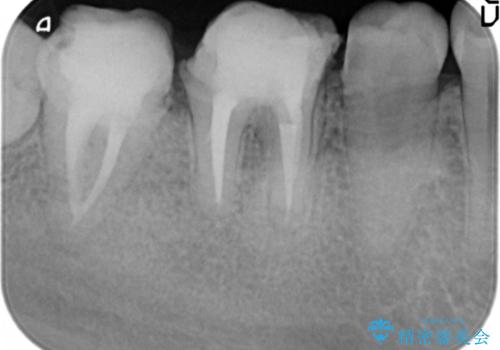

- 治療途中で放置してしまった奥歯の治療の続きを希望され来院されました。

奥歯は既に根管治療が為されクラウンを装着する必要性がある状態ですが、歯の高さが低くクラウンの安定性・強度を担保するために歯周外科を行う治療計画としました。

歯周外科を行うことで、歯ぐきの位置を下げ歯の高さを作り出し安定したクラウンの装着が可能となります。また同時に舌の邪魔となっていた骨隆起の除去を行うこととしました。